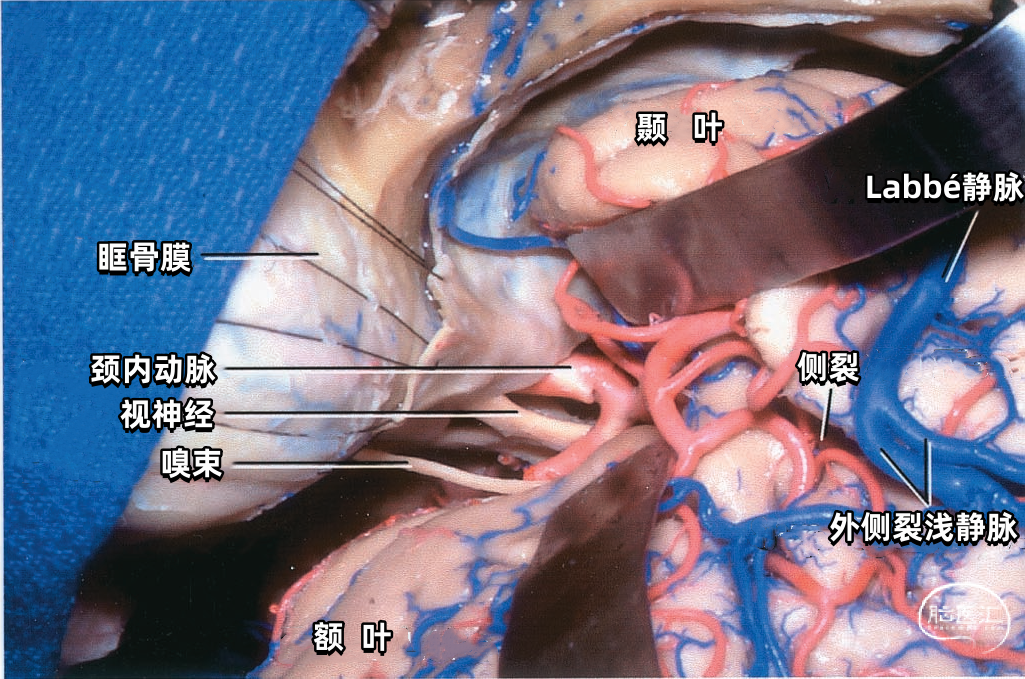

颞叶外侧面的皮层静脉可引流入横窦(上图),但在流入横窦之前,它们常向内沿颞叶底面进入小脑幕的短窦,此窦进入横窦末端之前在小脑幕内走行大约1cm。来自颞叶和枕叶底面的皮层静脉通常汇入外侧小脑幕窦。 Labbé静脉通常终于横窦(上图),但也可弧形围绕大脑半球下缘汇入外侧小脑幕窦。▼9.小脑幕窦

Labbé静脉也称下吻合静脉,是跨越颞叶外侧,连接外侧裂与横窦之间的最大吻合静脉。它通常起自外侧裂中部,行向后下,进入横窦前部。 Labbé静脉经过颞叶表面的位置有可能非常靠后甚至位于颞叶的最后界,或非常靠前达颞叶前1/3的外侧面。在此研究的20例半球中,12例Labbé静脉位于颞中静脉水平,6例位于颞后静脉水平,2例位于颞前静脉水平。有时会有两条Labbé静脉,其中后支通常会粗大一些。

下图示横窦和小脑幕窦的分支。抬起颞叶的后部,暴露进入横窦的Labbé静脉、颞后静脉和枕后静脉,从颞叶底面进入小脑幕窦的颞底静脉。

下图示放大观。从前方暴露Labbé静脉。从后部颞下入路手术,可能牺牲Labbé静脉和来自颞叶、枕叶外侧面的静脉,还可能需要牺牲多条汇入小脑幕窦的颞底静脉和枕底静脉。

下图示小脑幕的上面观。右侧Labbé静脉和颞后静脉直接引流入横窦。